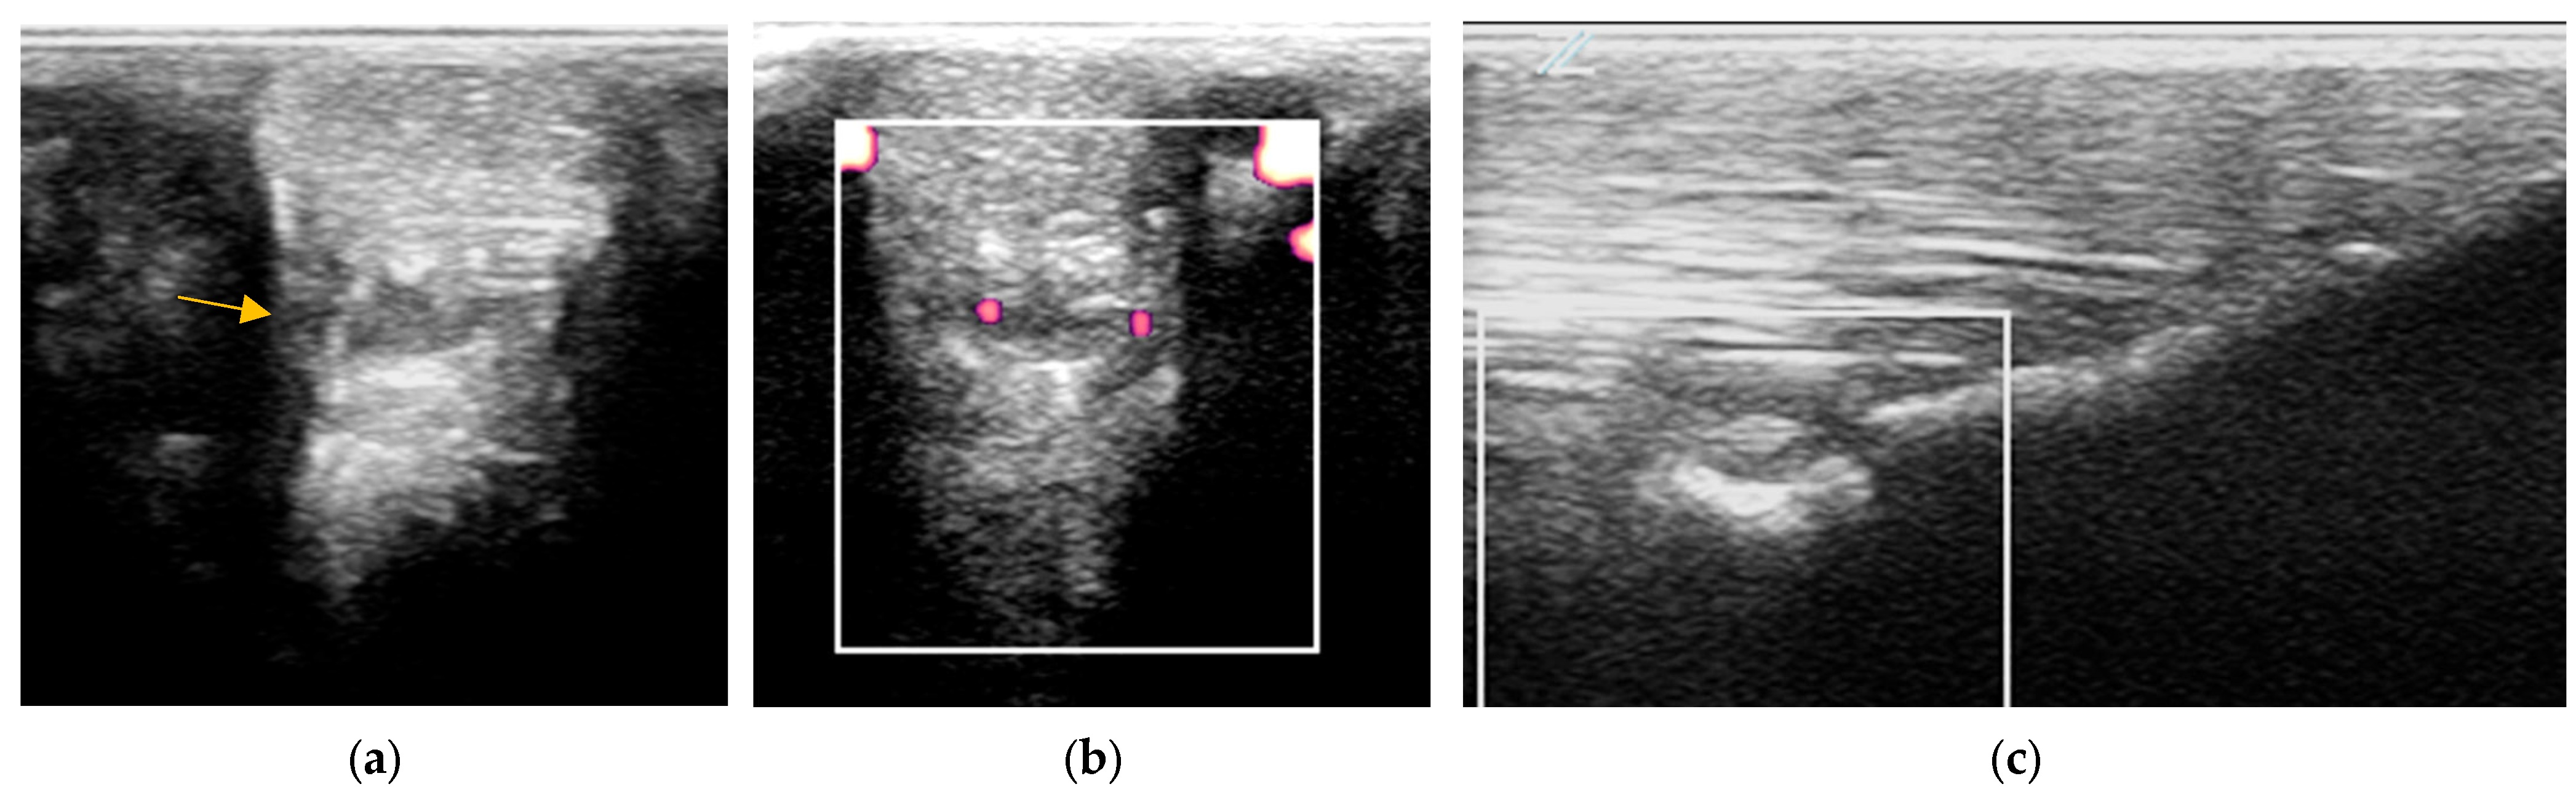

2.3.1. B-Mode Ultrasonography

2.3.2. Power Doppler Examination

4.4. Periligamentous Fibrosis